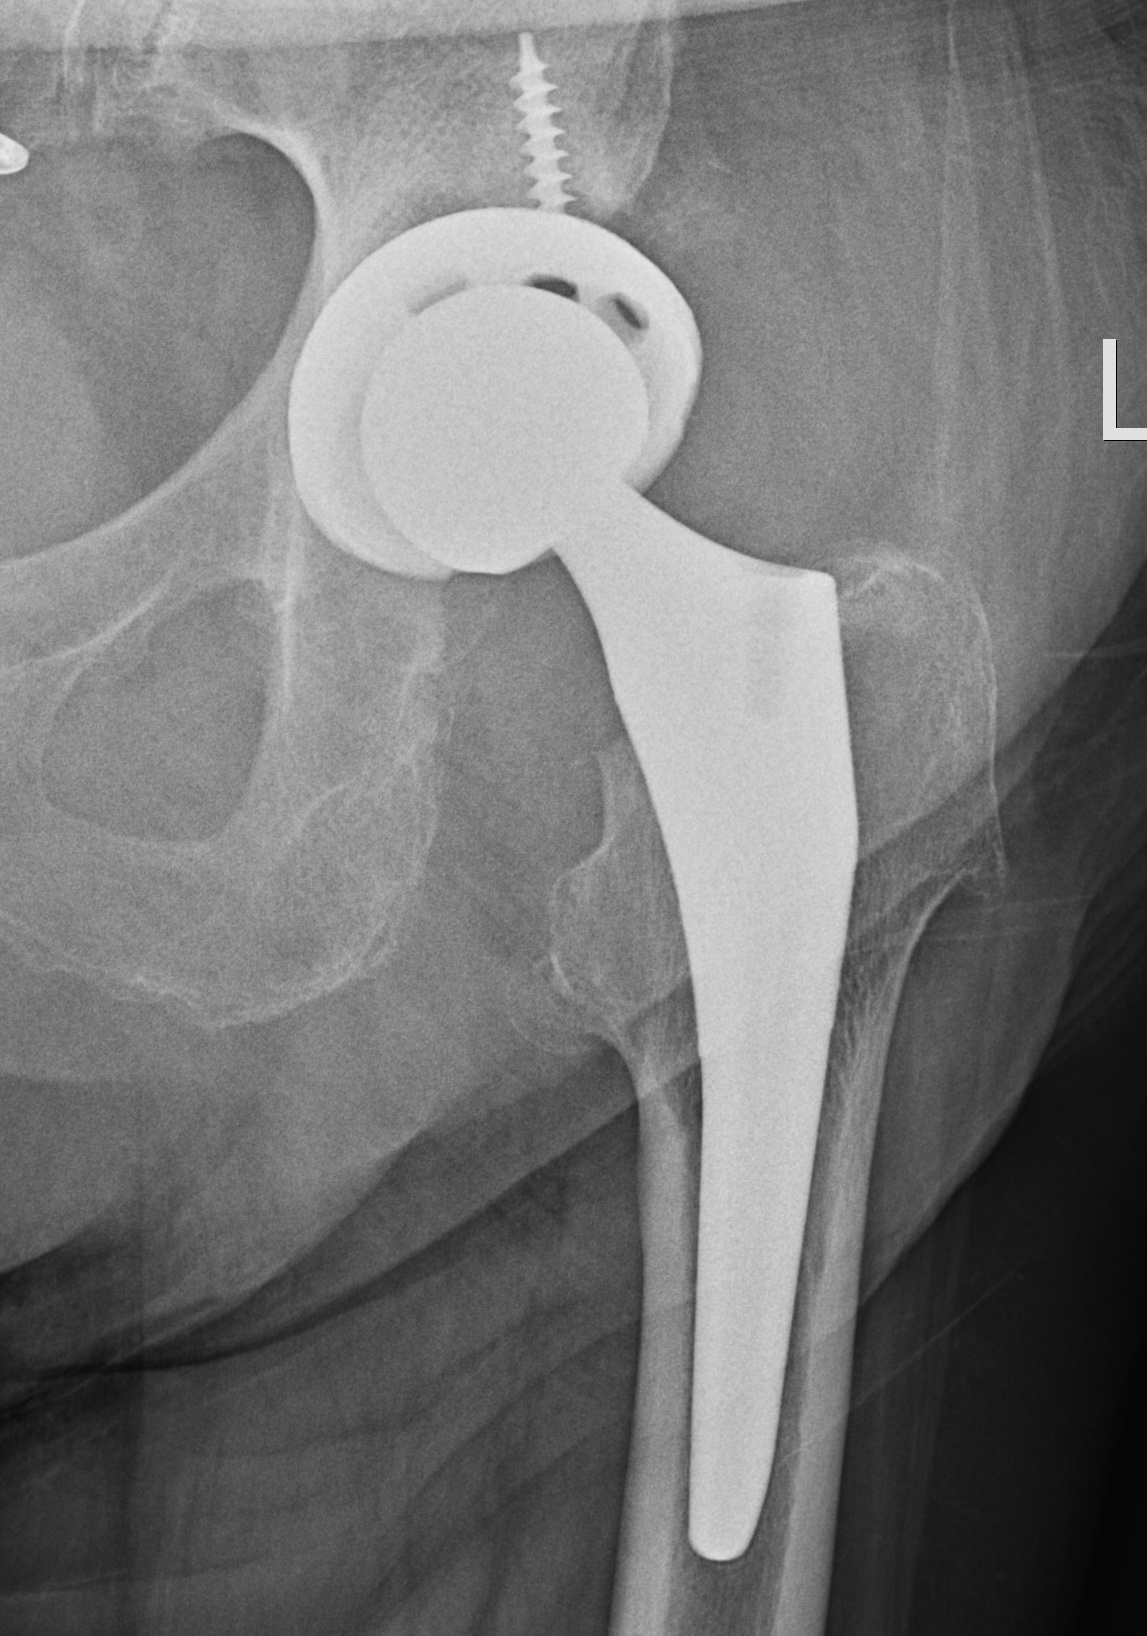

Femoral stem lysis Acetabular lysis